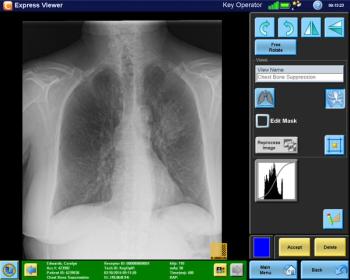

New image acquisition software from Carestream includes an FDA cleared bone suppression software feature.